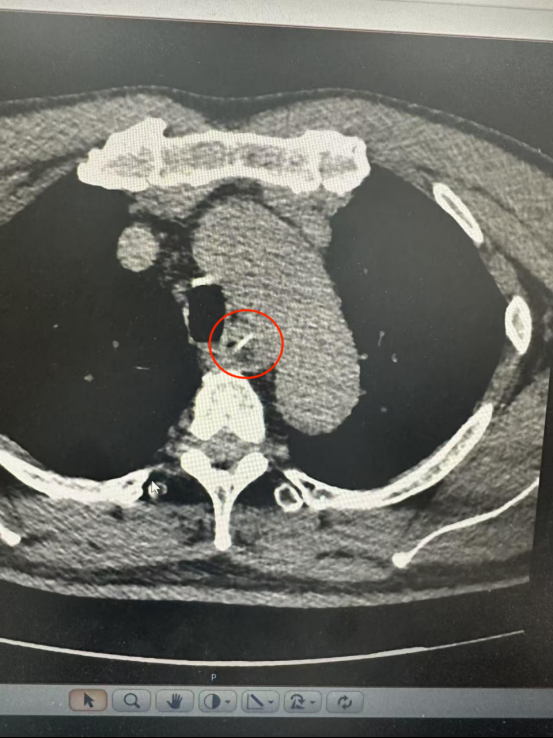

CT結果顯示一根長約25毫米的魚骨卡在食管中段,兩端分別緊貼食管管壁外緣與主動脈弓內側。主動脈是人體最粗大的動脈血管,魚骨所處位置極為危險。

根據CT三維重建結果,魚骨緊貼主動脈弓但未刺破主動脈及食管全層,尖端與主動脈切線垂直,呈“一”字型排列。